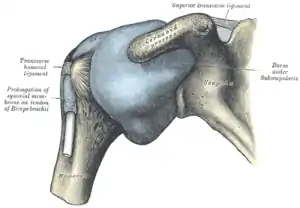

The right shoulder and shoulder joint | |

The shoulder joint (or glenohumeral joint from Greek glene, eyeball, + -oid, 'form of', + Latin humerus, shoulder) is structurally classified as a synovial ball-and-socket joint and functionally as a diarthrosis and multiaxial joint. It involves an articulation between the glenoid fossa of the scapula (shoulder blade) and the head of the humerus (upper arm bone). Due to the very loose joint capsule that gives a limited interface of the humerus and scapula, it is the most mobile joint of the human body.

The shoulder joint is a ball-and-socket joint between the scapula and the humerus. The socket of the glenoid fossa of the scapula is itself quite shallow, but it is made deeper by the addition of the glenoid labrum. The glenoid labrum is a ring of cartilaginous fibre attached to the circumference of the cavity. This ring is continuous with the tendon of the biceps brachii above.

Capsule

The shoulder joint has a very loose joint capsule, which can sometimes predispose the shoulder to dislocate.

Synovium extends below the long head of biceps and subscapularis tendon to form subscapular bursa. Therefore, long head of biceps is extrasynovial and intracapsular, attaching to supraglenoid tubercle.[4]

The shoulder joint is a muscle-dependent joint as it lacks strong ligaments. The primary stabilizers of the shoulder include the biceps brachii on the anterior side of the arm, and tendons of the rotator cuff; which are fused to all sides of the capsule except the inferior margin.[5]

The tendon of the long head of the biceps brachii passes through the bicipital groove on the humerus and inserts on the superior margin of the glenoid cavity to press the head of the humerus against the glenoid cavity.[5] Other long muscles such as pectoralis major, latissimus dorsi, teres major and deltoid muscles also provide support to the shoulder joint.[4]

- Superior, middle and inferior glenohumeral ligaments. It is the thickenings of the capsule that pass from the upper part of glenoid to lesser tuberosity and inferior part of the head of humerus. These ligaments are weak unlike its posterior part which is supported by the infraspinatus muscle.[4]

- Coracohumeral ligament[4]

- Transverse humeral ligament[4]